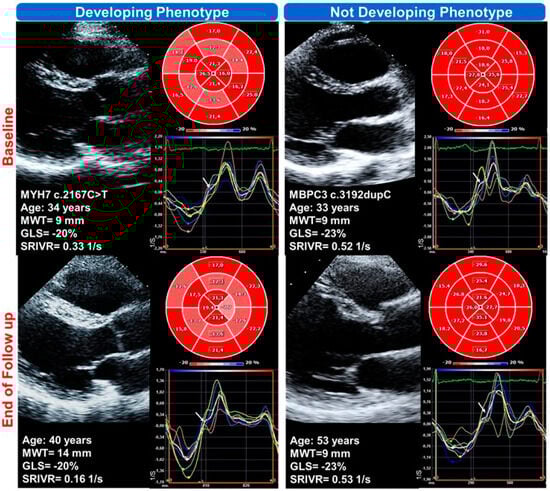

| AB | m | 34 | 1 | Son | MYH7 | c.2167C > T (p.R723C) | 40 | yes |

| VC | f | 33 | 12 | Sister | MYBPC3 | c.3192dupC (p.K1065QfsX12) | 54 | no |